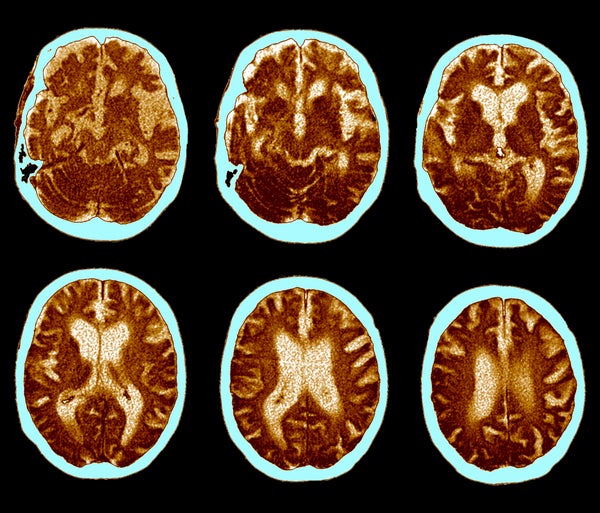

ЦТ мозга за Алцхајмерову болест.